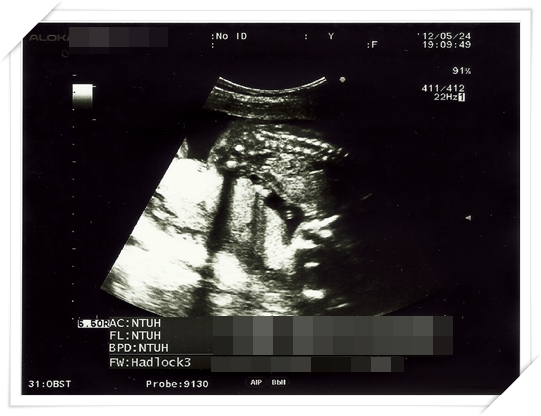

第19週的時候 又來到我們例行產檢的時候啦

照超音波的時候乖的跟甚麼一樣

只有意思意思打打嗝而已

雖然這樣醫生可以很快就順利量到小鴨的大小 頭圍 大腿骨的長度等等

不過事實證明 他長得很好啦~~~ 大小其實都還超前了真正的週數

而且我的週數本來就已經是矯正過後的週數 (依照大小往前推的週數)